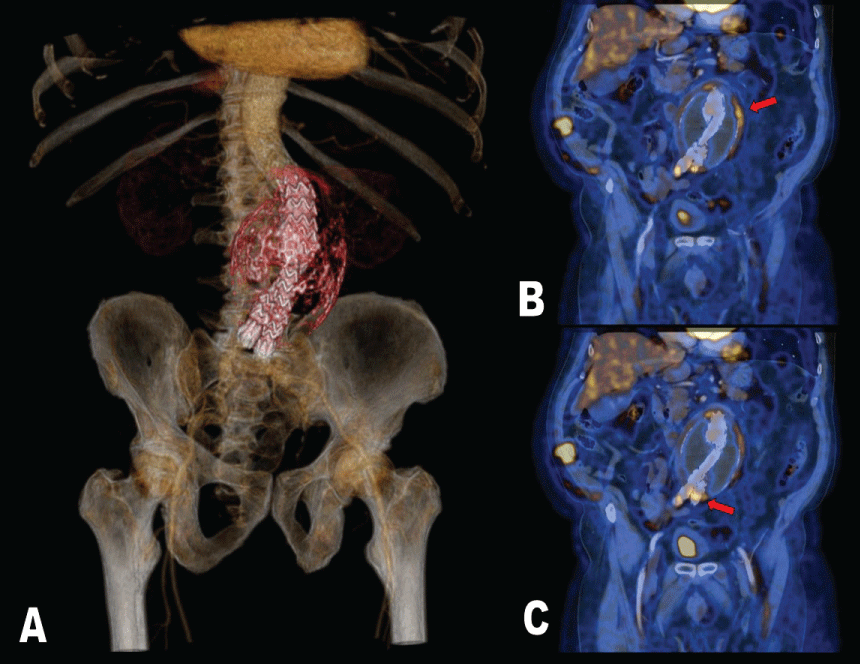

He was followed up during one year but fifty months later the angio CT revealed a juxtarenal abdominal aortic aneurysm excluded, with aortobiiliac endoprothesis, and a thrombosed aneurysm sac (Figure 1A) with a maximum size of 9 × 9.9 cm and true light of 25 mm; no signs of endoleaks or prosthesis related changes were observed but there was a paraaortic image to rule out inflammation so, a PET/CT was asked.

There was performed a 18F-FDG PET/CT study (Philips Gemini TOF) that showed not only a big infrarrenal abdominal aneurysm with areas of hypermetabolism on its wall (Figure 1B) but also hypermetabolic involvement in the distal part of the stent after the aortic bifurcation compatible with infection (Figure 1C).

Figure 1: A) PET/CT 3D reconstruction shows thrombosed aneurysm sac with aortobiiliac endoprothesis.

B) 18F-FDG PET/CT coronal view. Increased metabolic activity in the left side of the aneurysm sac wall (red arrow).

C) A focus with high glucose uptake was seen in the distal part of the stent after the aortic bifurcation compatible with infection (red arrow).